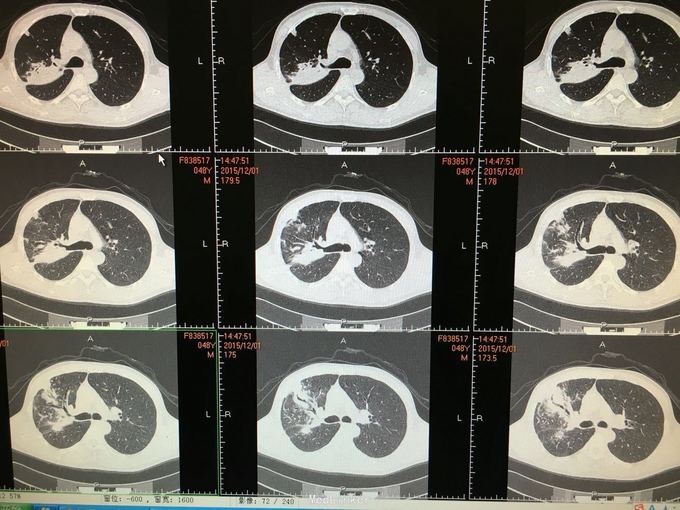

间断咳嗽咳痰5月余。患者缘于半年前确诊为骨髓增生异常综合征,并行造血干细胞移植术。术后出现发热,完善相关检查考虑为肺部真菌感染,给予抗感染治疗后体温正常,病情好转出院。出院后仍有间断咳嗽咳痰,咳黄色痰,无发热,自行口服伏立康唑200mg,2/日治疗,12月初复查CT提示双肺病灶较前进展,右肺中叶新增病灶。

根据症状体征及辅助检查,结合病史考虑真菌感染可能性大。进一步气管镜检查,结果如下。组织活检标本可见。病理回报提示真菌团,培养见曲霉菌生长。明确诊断后给予两性霉素B雾化吸入及伏立康唑静脉应用抗真菌治疗,同时给予环孢素口服。

造血干细胞移植后肺部感染常见,其中以曲霉、卡肺等多见,患者经气管镜检查已将真菌团块取出。术后给予监护,口服云南白药、垂体后叶素雾化止血等治疗,无明显出血,症状逐渐好转。复查CT也明显好转。